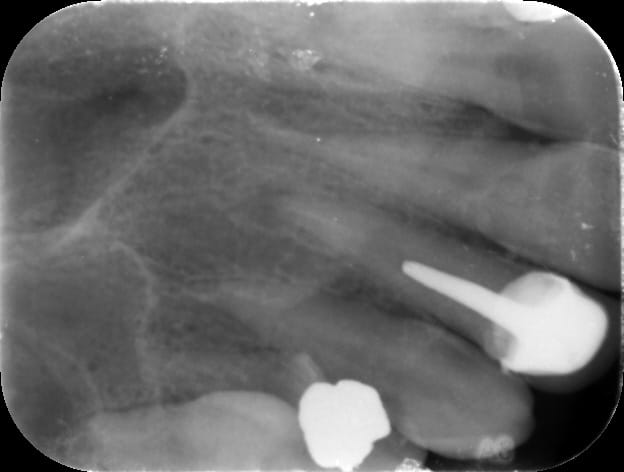

Qu'est ce que vous faites dans le cas de gros tenons comme là bande de vieilles branches ? 22 et 12 sur la même patiente

Img 0702 yvtk5b - Eugenol

Img 0703 xwhbb3 - Eugenol

Merde 😊😊😊 j'attendais avec impatience que quelqu'un me dise de faire une obturation à rétro . T'as complètement raison on retire les IC.

Img 0701 bf7cie - Eugenol

Img 0700 iso1ck - Eugenol

Treponem

25/01/2017 à 21h19

GG

Tu as déposé à l'arrache couronne ? C'est couillu ...

Moi, j'ose pas je taille dans le gras.

Bin pourquoi t'as pas fait une ERI?